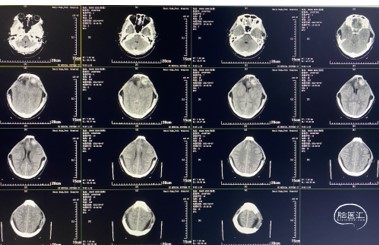

影像学检查

入院时(2021-05-19)头颅CT检查提示:双侧额颞叶点状脑挫裂伤,蛛网膜下腔出血,脑肿胀,侧脑室、三脑室缩小,环池少量积血,中脑轻度受压;